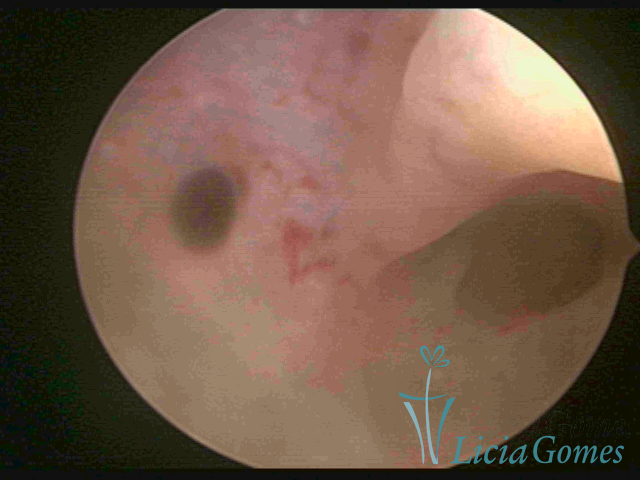

ADENOMIOSE

É a presença de tecido endometrial na camada muscular do útero

A vídeo-histeroscopia permite diagnosticar às lesões próximas às camadas miometriais superficiais, próximo ao endométrio visualizando lesões de coloração violácea, circunscritas, ou acastanhadas com conteúdo achocolatado.